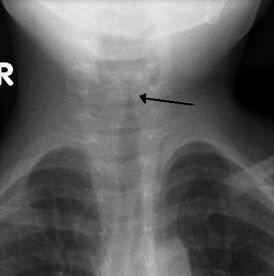

Может быть информативна рентгенография гортани. У детей с крупом при рентгенографии в боковой проекции может визуализироваться отёк гортаноглотки с сужением подскладочного пространства гортани (в прямой проекции имеющим вид классического симптома «остро заточенного карандаша»)[3].